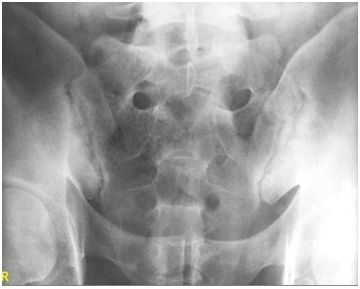

6. 19歲男性最近半年覺得早上起床時下背有酸痛及僵硬發生達一小時之久,骨盆X-光發現有異常如圖。請問下列何種藥物對疾病治療最為有效? (A) Anti-TNF-alpha therapy (B) Salazopyrin (C) Azathioprine (D) Prednisolone (E) Hydroxychloroquine